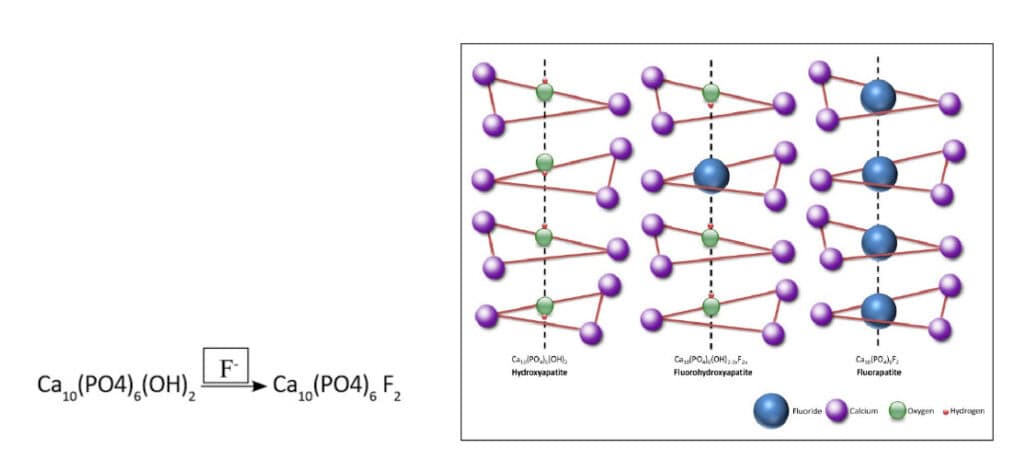

Topical fluoride can make the Hydroxyapatite structure in enamel more resistant to acid breakdown but ONLY when indicated and when used strategically, minimally, and responsibly.

With controlled topical application of medically compounded products to teeth, fluoride can be incorporated into the Hydroxyapatite (HAP) tooth matrix, replacing a hydroxyl group (OH), to create Fluorohydroxyapatite (F-HAP). If we have uncontrolled demineralization and/or dental decay, responsible and topical use of fluoride can provide some additional protection to the tooth matrix. Controlled and responsible.

- F-HAP is more resistant to the stripping demineralization in an acidic oral environment.

- For active tooth decay and uncontrolled pH balance of the mouth with predominant demineralization, a very controlled and strategic topical use of medically compounded sodium fluoride (NaF) can help to tip the scales to remineralization.

- Too frequent fluoride exposure, particularly during tooth development, can go too far and replace all of the OH groups in HAP to create Fluorapatite which is brittle and more at risk of fracture, as it does not have the flexure of natural Hydroxyapatite or Fluorohydroxyapatite.